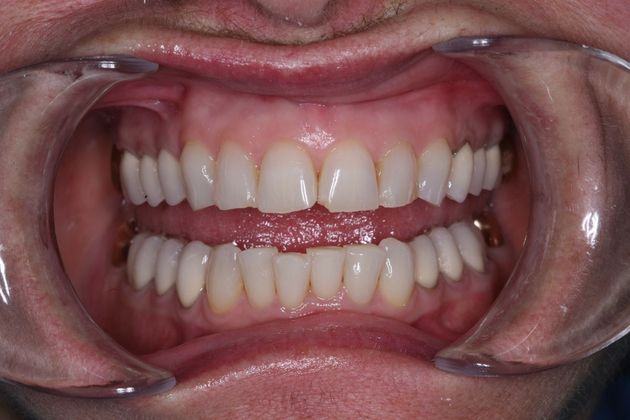

Procedures; TMJ CAT scan, TMJ deprogramming, whitening, sedation dentistry, reconstruction of all the back and upper front teeth with porcelain crowns, bite guard therapy. This foster care provider wanted to be free of the pain in her jaw joints. She had a lifelong history of grinding, many of her back teeth were breaking down and her bite was off. Her treatment was performed in sections to spread out the cost. She and her husband were so pleased with the result!